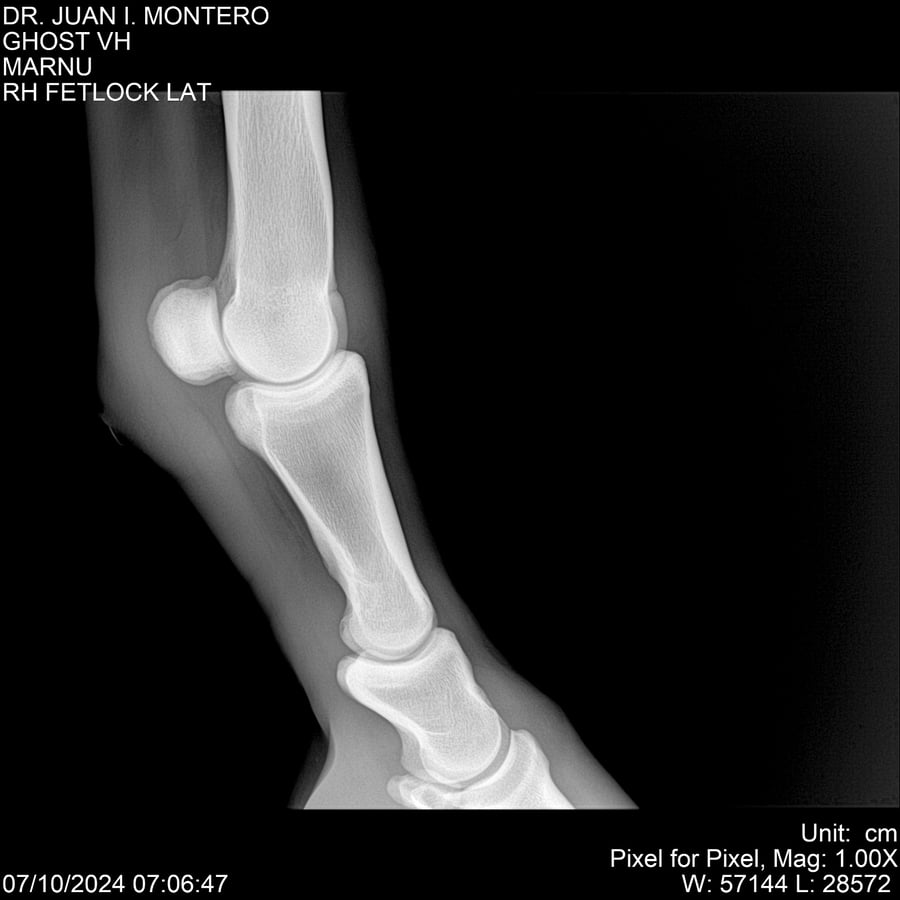

LOTE 15, GHOST VH 🔥 🔥 🔥 Lote Anterior Volver al remate Lote Siguiente Ficha Contacto Montevideo - Ficha del Lote Identificador: #282525 Categoría: Yeguarizos Montevideo - 69 Visualizaciones ClicData Contacto Empresa: Abelenda N. R., Walter Hugo Nombre*: Teléfono* : E-mail* : Mensaje Enviar Registrese gratis Este contenido Exclusivo está disponible sólo para usuarios registrados Ingresar